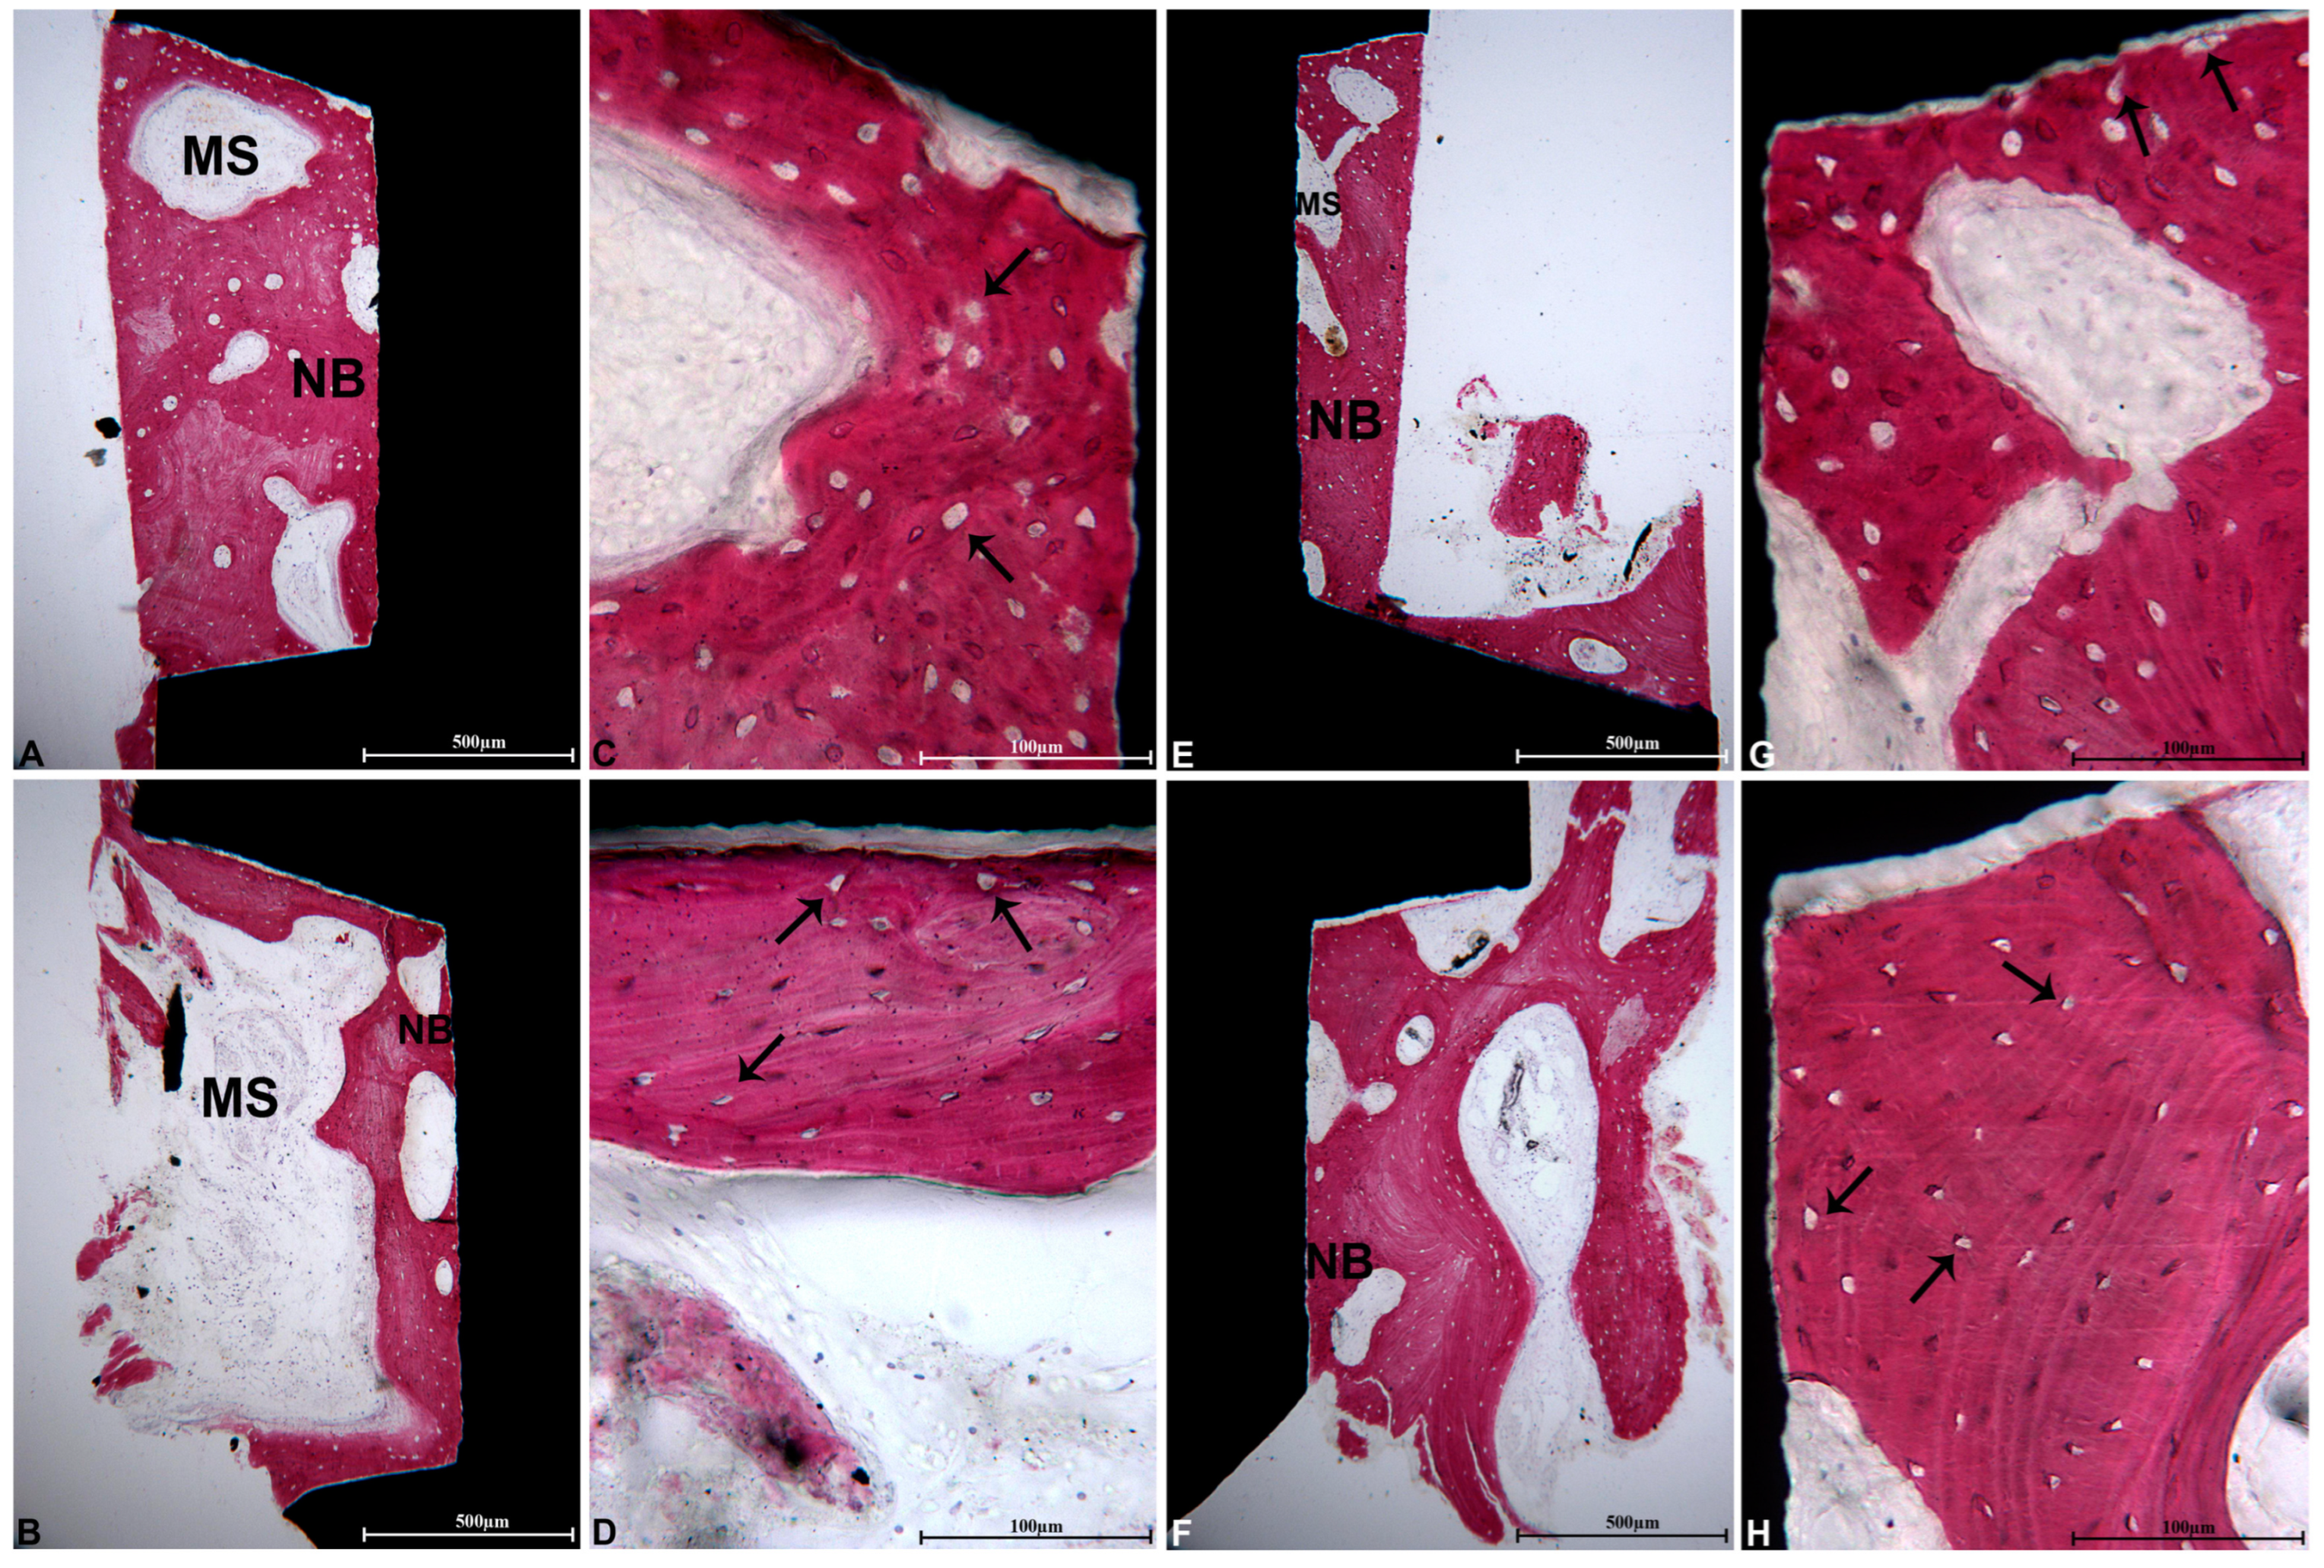

2.2. Histological Processing and Analysis

2.3. Collagen Fiber Orientation Observed with Polarized Light Microscopy

3. Results